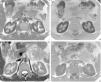

(A) Axial T2 sequence image. Diffuse low signal of the renal cortex compared to the liver and skeletal muscle. (B) Axial T1 in-phase sequence also shows low signal of the renal cortex compared to the liver and skeletal muscle. (C) MR of the same patient 14 months after start of treatment. Axial T2 sequence image shows important improvement of the low signal on T2. (D) Axial T1 in-phase sequence confirms the important increase of the renal cortex signal compared with the previous MR study.

Renal function was normal, serum creatinine 0.9mg/dl and FG (MDRD)> 60ml/min. Persistent hemoglobinuria with normal urinary sediment. Proteinuria 1.3g/day with albuminuria 170mg/day and non-selective aminoaciduria, thus indicating PTD. The acid-base status, phosphate and uric acid were normal. The possibility of PTD due to hemosiderin deposition was considered, so an MRI was performed, finding hypointense bilateral renal cortical compatible with iron deposition (Fig. 1A and B). Eculizumab therapy was considered, but he was not eligible because lack of transfusion requirement, and normal GFR.

Fourteen months after the start of eculizumab a new MRI showed improved hypointense signal in the renal cortex of 34% and 51% in the left and right kidney respectively, indicating the partial removal of iron deposits in the kidney (Fig. 1C and D).